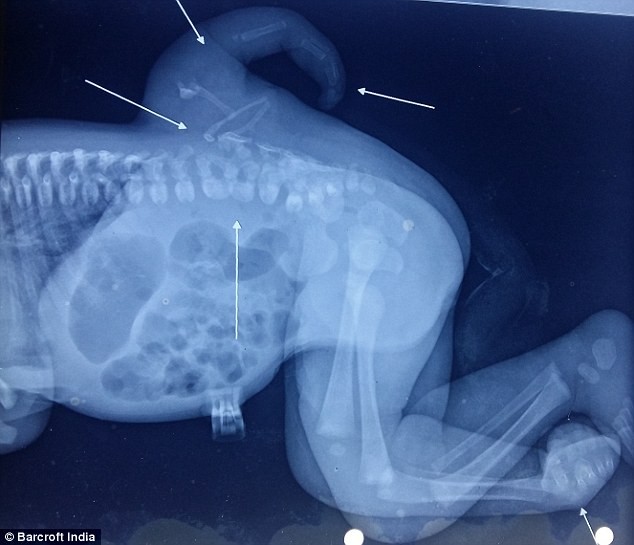

Các bác sĩ cho biết, bé Varsha mắc một chứng bệnh khá hiểm gặp gọi là polymelia. Dị tật bẩm sinh này khiến trẻ em sinh ra với chi thừa, thường là cánh tay hoặc cánh chân. Theo đó, chứng bệnh polymelia này thường chỉ phát triển trong quá trình phôi thai.

“Nguyên nhân có thể do phôi thai phát triển thành cặp song sinh dính liền nhau nhưng một trong hai thai nhi ngừng phát triển, để lại những phần thừa, thường là các chi trên cơ thể của em bé còn lại”, bác sĩ Daljit Singh, người điều hành ca mổ cho biết.

![]() |

Hình ảnh chụp X-quang cho thấy chi thừa của bé Varsha.